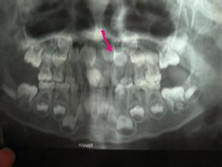

多生牙

多生牙的大小和形状可能与其磨牙、前磨牙或前牙组中的牙齿非常相似,也可能与相邻牙齿...

X线平片、口腔科检查